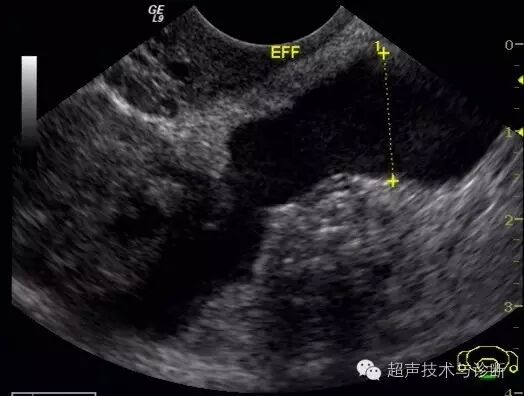

盆腔扫查见1.4cm积液。

入院血HCG及超声检查图像如下;